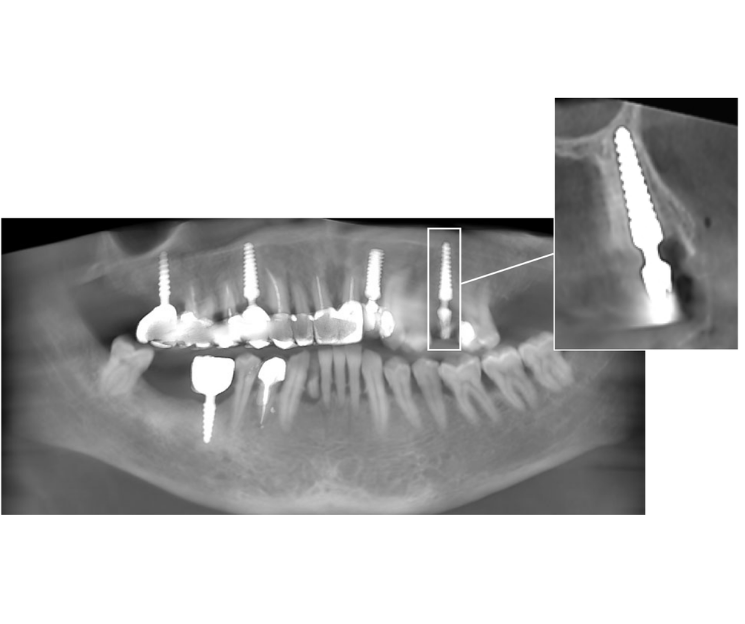

Se optó por un implante monofásico compresivo. La indicación se basó en dos criterios fundamentales:

- Volumen óseo adecuado: Existencia de un lecho receptor con hueso sano.

- Búsqueda de estabilidad primaria: Este tipo de implante permite condensar el hueso esponjoso durante la inserción, aumentando su densidad y logrando una excelente estabilidad primaria, requisito indispensable para la rehabilitación inmediata.